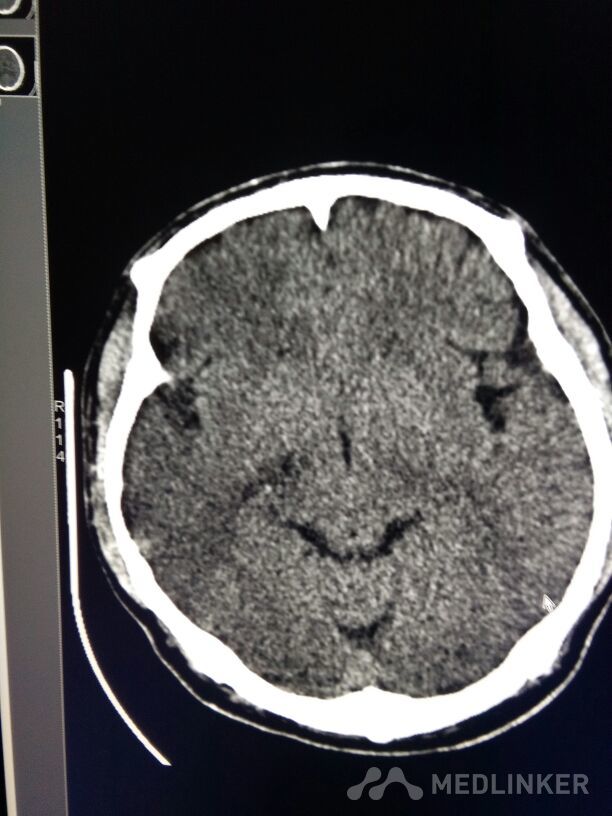

考虑表皮样囊肿?

放射科检查

表皮样囊肿